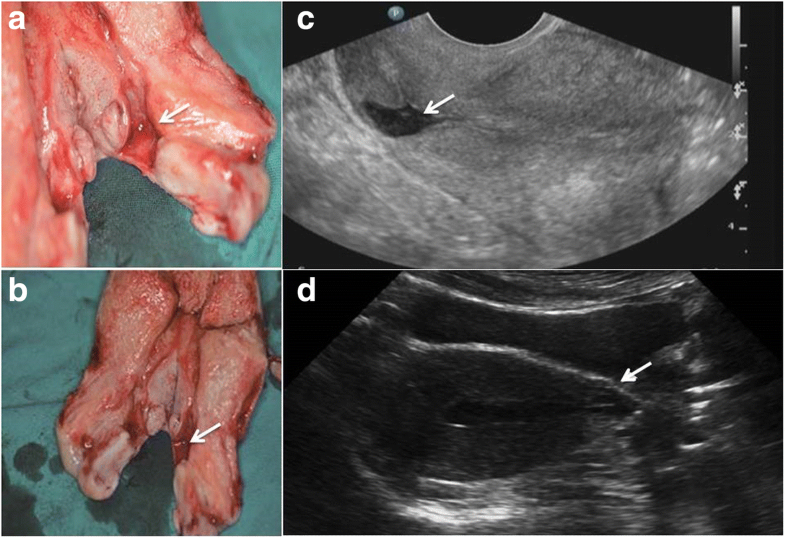

From bmcpregnancychildbirth.biomedcentral.com

Obstetrical after vaginal repair of caesarean scar diverticula in reproductiveaged Bv Infection After C Section infections that develop after delivery of a baby (postpartum infections) usually begin in the uterus. bacterial vaginosis is associated with increased vaginal concentrations of certain anaerobic and facultative bacteria. (after a vaginal birth, it's possible to have one at the site. gynecologic procedures pose a unique challenge in that potential pathogenic microorganisms from the skin. bv. Bv Infection After C Section.